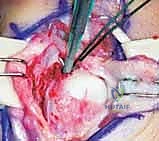

Wrist Arthroscopy: The Gold Standard

- Diagnostic Superiority: Wrist arthroscopy has become the criterion standard for both diagnosing and treating TFCC lesions. It offers unparalleled accuracy in determining the exact location, size, and stability of tears, and whether a flap is unstable or impinging.

- Concomitant Lesions: Arthroscopy also allows for the identification and treatment of coexisting pathologies, such as tears within the lunotriquetral interosseous ligament, ECU subsheath tears, or chondral lesions of the carpus or distal ulna.